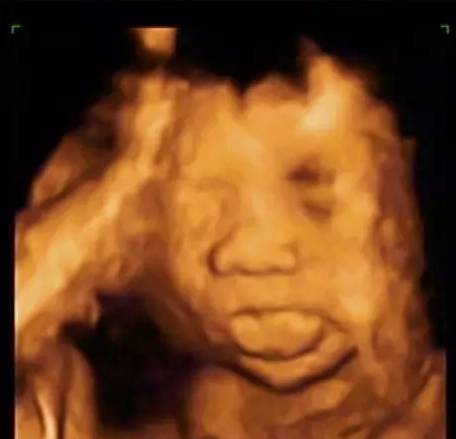

23周胎儿真实图片欣赏

23周胎儿真实图片欣赏,18周真实胎儿图片欣赏

看图上只是一个23周的胎儿,当然也可以有非常丰富的表情.

怀孕23周3d胎儿图